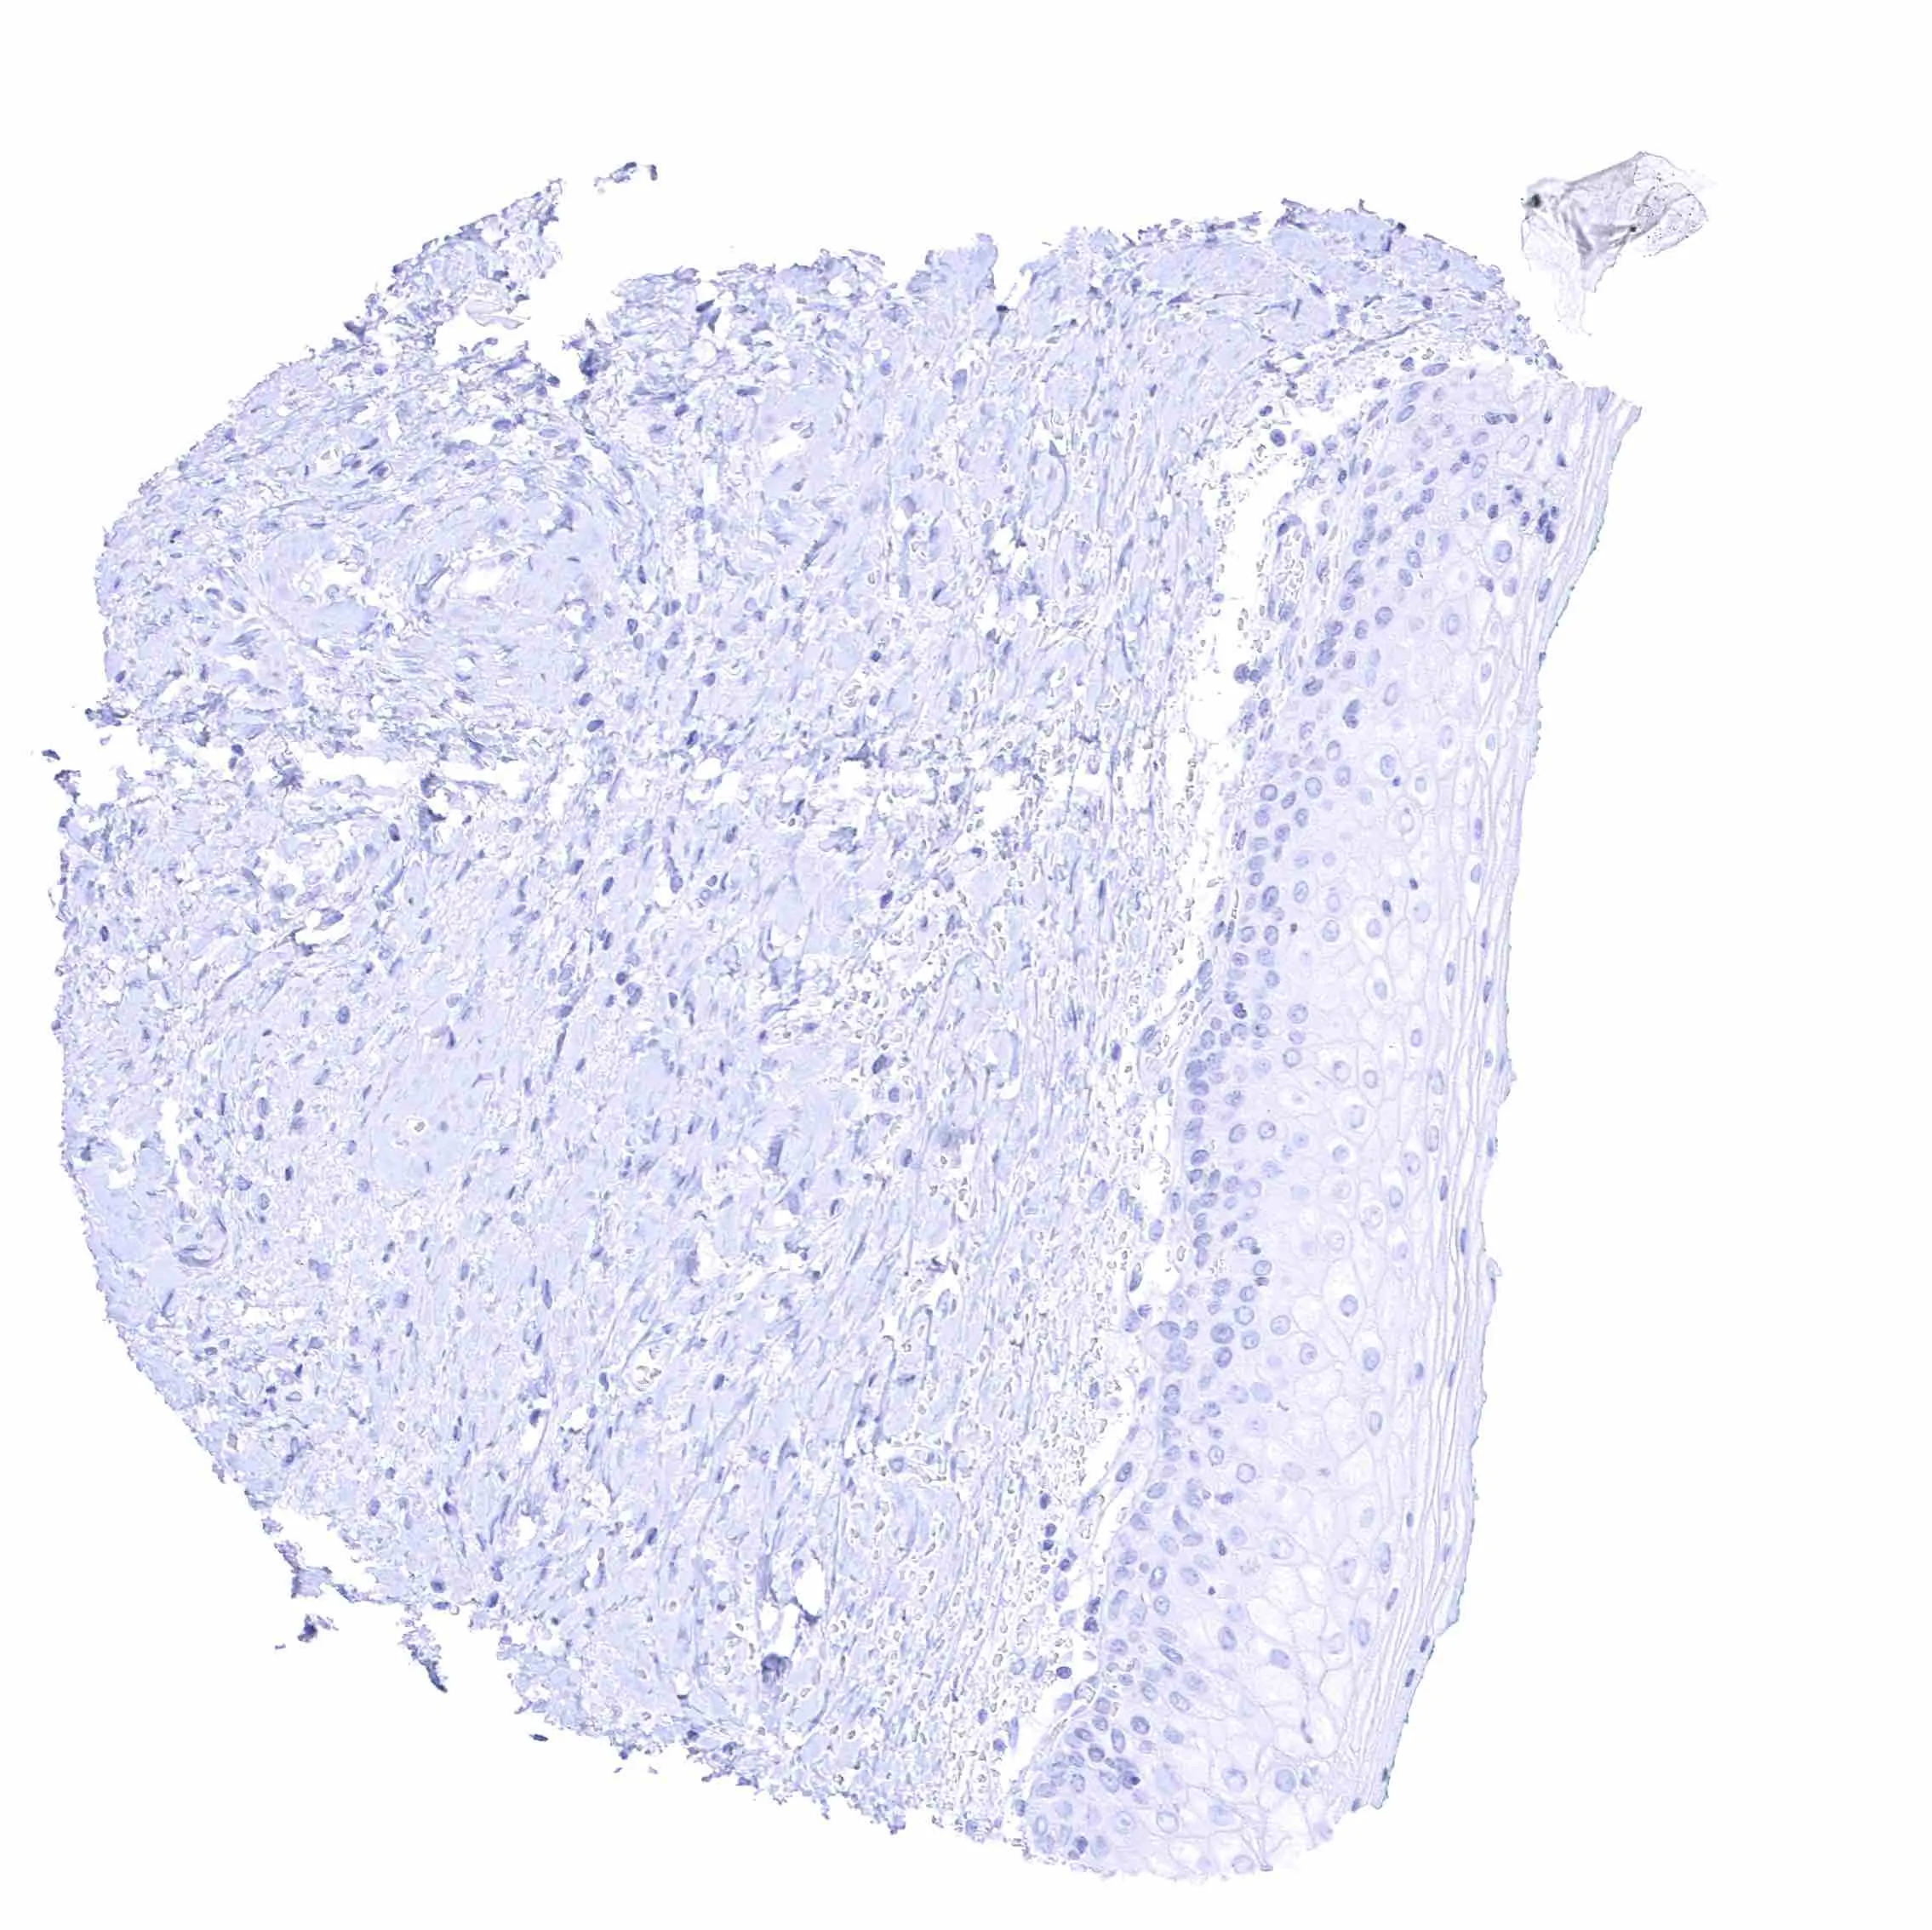

Skin

Uterus, ectocervix